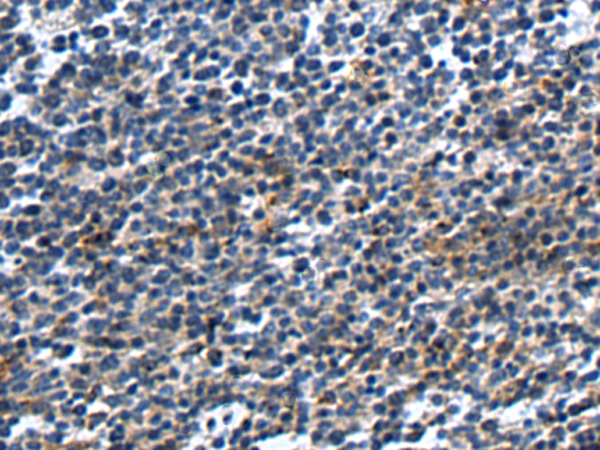

分类: 科研抗体货号: P09456别名: B70; B7-2; B7.2; LAB72; CD28LG2应用: WB,IHC反应种属: Human